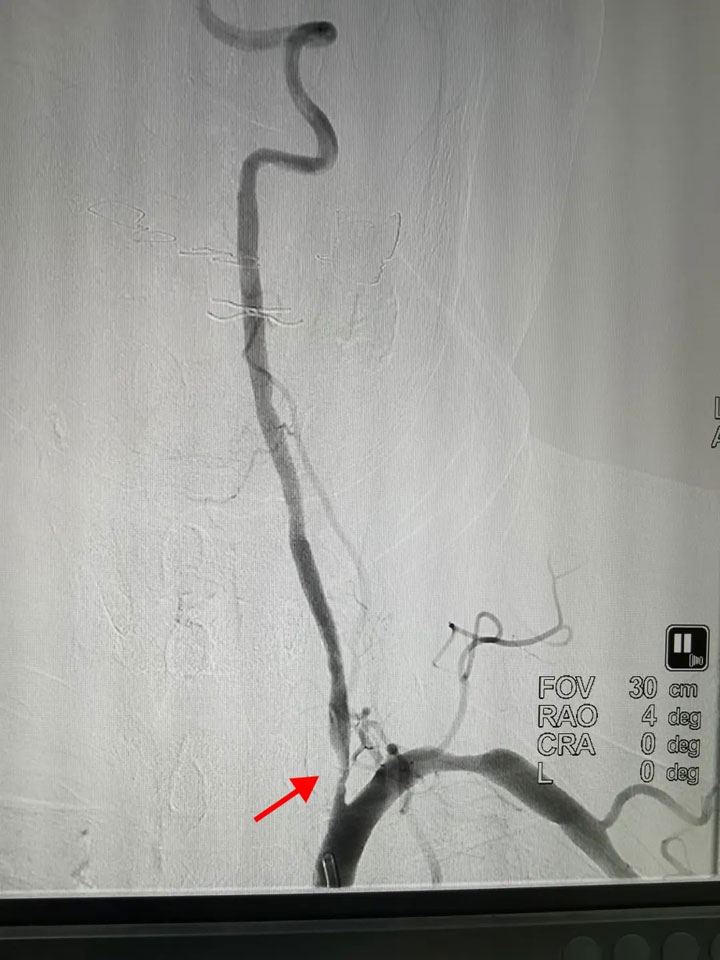

在医生熟练的操作下,导丝灵巧的穿梭,顺利进入颈总动脉等目标部位。在DSA的辅助下,造影剂将所经过的血管轨迹记录。脑内血管如同一张精密的网络清晰地显示在屏幕上,病变部位被准确标记。明确诊断后,规范治疗的杨师傅很快好转。